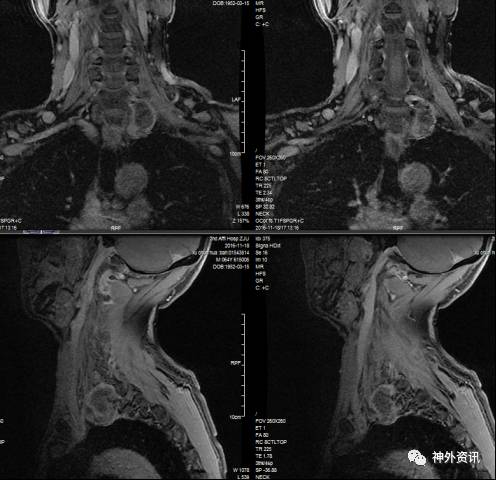

入院后进一步行增强MRI检查,显示胸1左侧椎旁间隙可见大小约为24.9x34.2x37.8mm(左右x前后x上下)等T1长T2异常信号影,增强后不均匀轻度强化,其内未见脂肪信号,部分向内进入颈7-胸1椎间孔,椎间孔扩大。周边与颈总动脉、锁骨下动脉关系密切。肿瘤大体位于胸骨切迹以上,最低水平位于左侧胸膜顶,向胸腔突入(图1)。影像诊断:颈胸交界区左侧椎旁间隙肿块,考虑臂丛神经鞘瘤。

图1. 术前MRI可见肿瘤位于颈7-胸1水平,不均匀轻度强化。部分向内进入颈7胸1椎间孔,椎间孔扩大。肿瘤大体位于胸骨切迹以上,最低水平位于左侧胸膜顶,向胸腔突入。